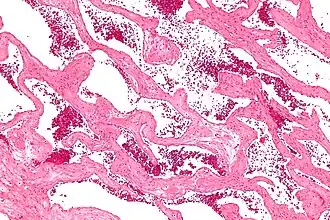

| Microfotografia de um hemangioma hepático cavernoso | |

Hemangioma cavernoso, também chamado de angioma cavernoso, cavernoma ou cavernoma cerebral (quando se refere à presença no cérebro)[1][2] é um tipo de tumor vascular benigno ou hemangioma, em que uma coleção de vasos sanguíneos dilatados (aneurismas) formam uma lesão.[3]

Hemangioma cavernoso hepático

Os hemangiomas cavernosos são os tumores benignos mais comuns do fígado.[14] Normalmente existe um tumor, mas múltiplas lesões podem ocorrer no lobo esquerdo ou direito do fígado em 40% dos pacientes.[4]